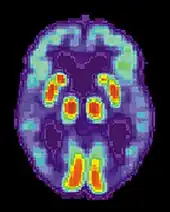

La maladie d'Alzheimer est caractérisée par une perte de neurones et de synapses dans le cortex cérébral et certaines régions subcorticales. Cette perte anormale entraîne une atrophie des régions affectées, incluant le lobe temporal, pariétal et une partie du Lobe frontal et du gyrus cingulaire[61]. Le cerveau peut ainsi perdre 8 à 10 % de son poids tous les dix ans, contre 2 % chez un sujet sain. L'atrophie corticale s'accompagne d'une dilatation des ventricules cérébraux et des sillons corticaux ainsi que d'une perte neuronale affectant particulièrement le système cholinergique (noyau basal de Meynert, septum, cortex entorhinal, amygdale et hippocampe).

Les études utilisant l'IRM et le PET scan ont documenté une réduction de certaines régions spécifiques chez les personnes atteintes de la maladie d'Alzheimer lorsqu'elles progressent d'un trouble cognitif léger vers une maladie d'Alzheimer, en comparaison des images de sujets sains âgés[62],[63].

- La Tomographie par émission de positons (TEP)

Elle permet de mettre en évidence un hypo-métabolisme (c'est-à-dire un fonctionnement moins efficace du cerveau) et de visualiser les lésions cérébrales caractéristiques de la maladie, notamment les plaques amyloïdes.